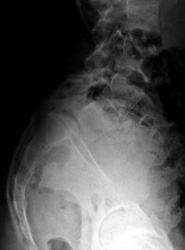

This lateral X-ray of the lumbrosacral spine demonstrates the forward shift in the fifth lumbar vertebra on the sacrum (L5-S1 spondylolisthesis).

(Courtesy of Texas Scottish Rite Hospital for Children)